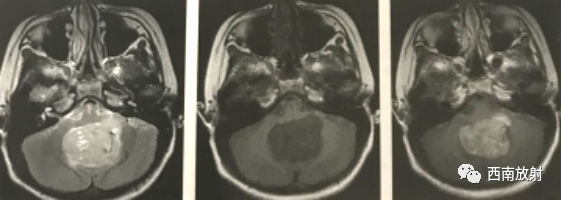

MRI不仅能明确肿瘤大小、形态、信号及其与周围结构的关系,还能与其他肿瘤鉴别诊断。肿瘤的实质部分多表现为长T1、长T2信号,增强扫描时实质部分显著强化(图);第四脑室常被向前推移,变形变窄;大部分患者合并幕上脑室扩张及脑积水。MRI较CT有一定优势,能清楚显示肿瘤与周围结构及脑干的关系,矢状面或冠状面的增强T1WI易显示沿脑脊液种植的病灶。

▲图 髓母细胞瘤。轴面T2WI及T1WI显示肿瘤位于小脑蚓部,形态欠规则,边界清楚,第四脑室前移;轴面增强TW显示肿物不均匀强化。